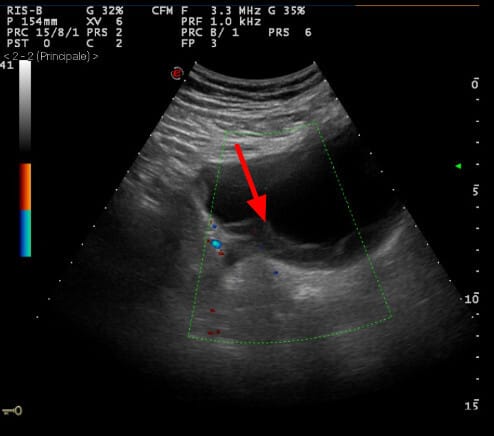

고환암 영상 소견

– 신체검사: 단단한 고환 종괴 촉지.

– 종양표지자: hCG 상승 가능, 그러나 AFP는 정상

– 영상검사: 고환 초음파에서 저에코성 종괴 확인.

– CT/MRI: 병기 설정 및 전이 평가.

– 확진: 고환 절제술(근치적 고환 절제술, radical orchiectomy)을 통한 조직학적 확인.